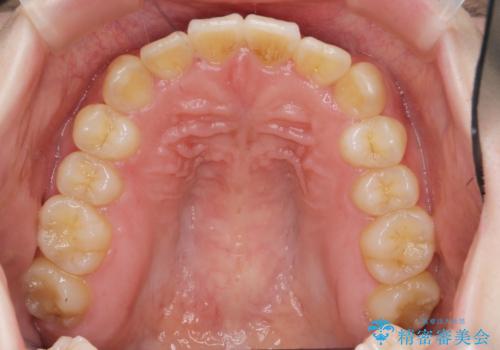

- ねじれの目立つ前歯を改善したいと、矯正治療を希望され来院されました。

インビザラインの不得意な上顎前歯のねじれの改善を、マウスピース矯正を行う前に前歯のみの部分ワイヤー矯正を行うことで治療期間の短期化を目指します。

上顎前歯のねじれはマウスピースで治りづらいため、マウスピース矯正の治療期間の長期化をきたしやすい歯列不正です。

マススピース矯正を始める前に、部分ワイヤー矯正を行うことで治療の短期間化・良好な仕上がりを達成することができました。